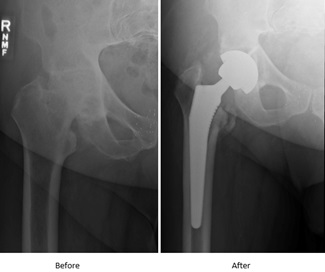

After seeing a location orthopedic doctor in Frederick, Rudolph found out his hip needed to be replaced. He was told bone was rubbing on bone, and his only option was surgery, more specifically, a hip replacement.